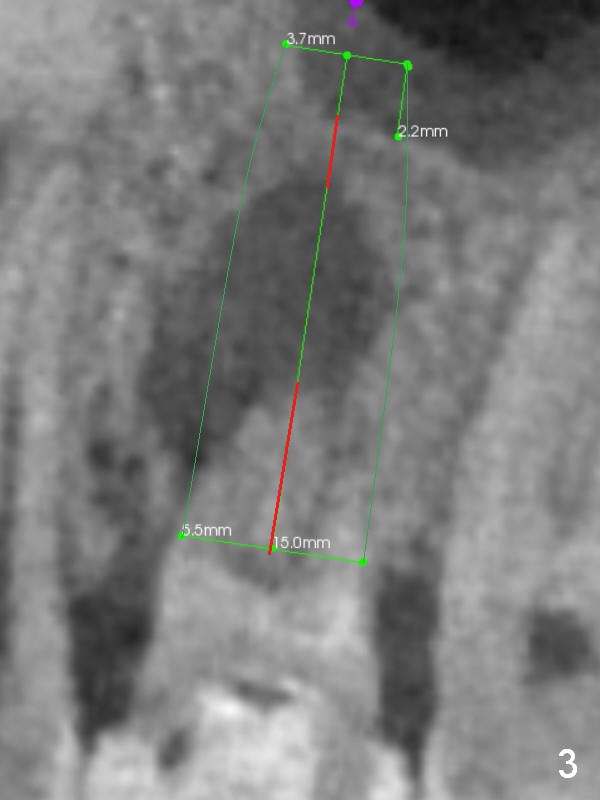

A 34-year-old man has persistent large periradicular radiolucency (Fig.1) after root canal therapy with a fistula (Fig.2). It appears that immediately after extraction (no Antibiotic) a long implant (15 or 16 mm, green outline) should be placed to bypass the bony defect with 2-point fixation (septum and sinus floor; Fig.3 (CBCT sagittal section), 4 (coronal section) red line). A shorter implant, which is placed at the septum (4-5 mm tall), is not expected to be stable. The diameter of the implant is to be determined after sequential osteotomy. The minimal will be 4 mm (Fig.5 axial section) as long as the implant or osteotomy does not perforate the palatal (P) or buccal (B) socket substantially. The bone density at the septum and the sinus floor is 1100 and 200-400 units, respectively. Drills and osteotomes (Tatum or Magic Expanders) will be used for osteotomy in these 2 segments, respectively.